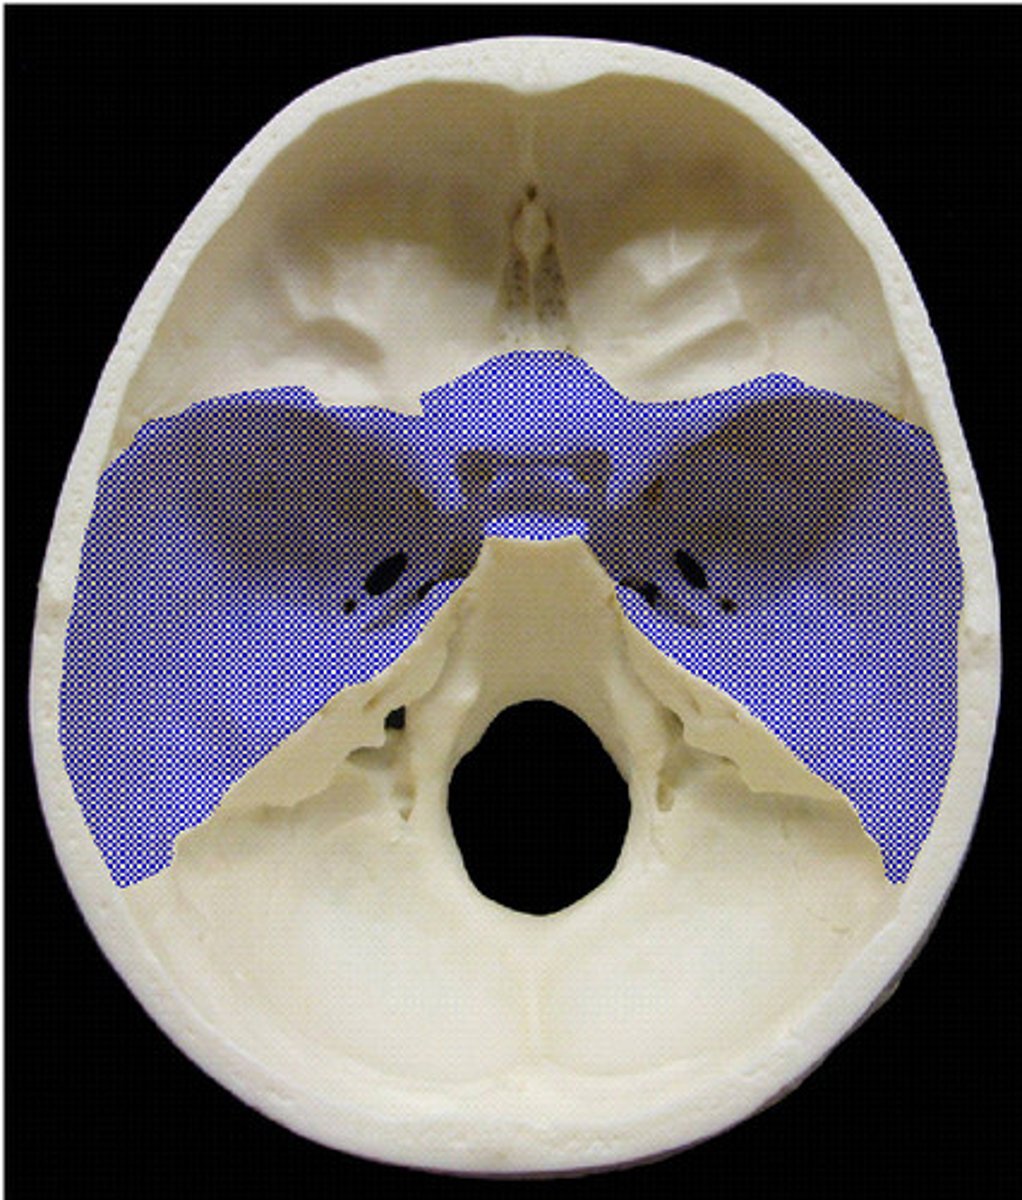

middle cranial fossa